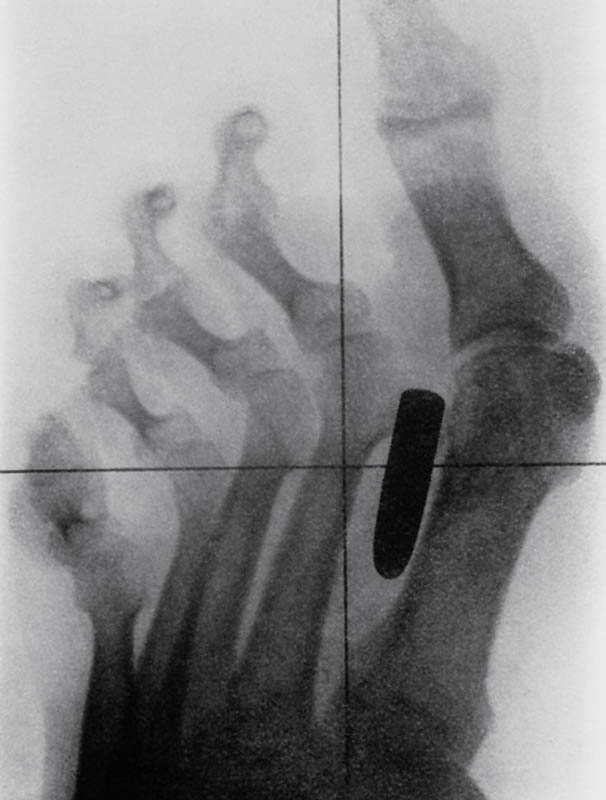

Гвоздь в костях указательного и среднего пальцев взрослого мужчины